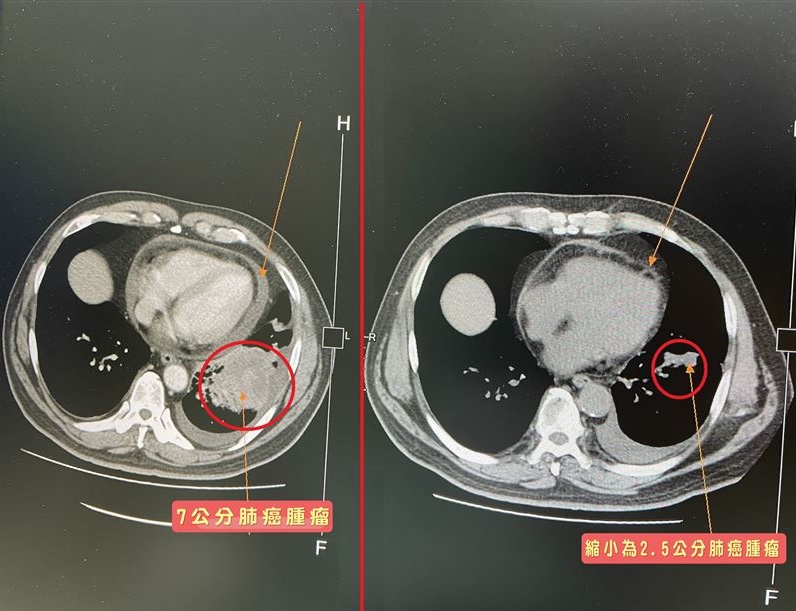

Chụp X-quang phát hiện bóng mờ bất thường ở thùy dưới phổi trái. CT ngực phát hiện khối u 7cm kèm tràn dịch màng phổi, di căn sang phổi phải, hạch bạch huyết và tuyến thượng thận. Đáng lo hơn, ông còn có lượng lớn dịch màng ngoài tim. Khi dịch tích tụ quanh tim, tim bị chèn ép, khả năng bơm máu giảm, gây khó thở, tức ngực và có thể ngừng tim đột ngột.

Khi nhập viện, ông phải dẫn lưu khẩn cấp 800ml dịch máu từ màng ngoài tim. Sau đó, sinh thiết xác nhận ung thư biểu mô tuyến phổi. Ông được hóa trị ngay, sau 4 đợt khối u thu nhỏ còn 2,5cm, triệu chứng tức ngực cải thiện rõ rệt. Tuy nhiên, tiên lượng của ông vẫn rất xấu do phát hiện muộn và có nhiều bệnh lý khác cùng lúc.